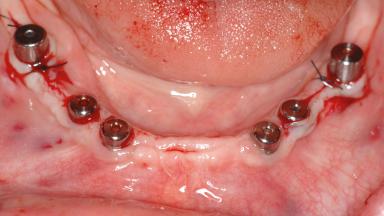

A 47-year-old woman who had suffered from aggressive periodontitis requiring a number of periodontal interventions over more than 10 years was referred by her general dental practitioner and periodontologist for bone augmentation and implant therapy. Her failing dentition had already been scheduled for extraction. The patient expressed a desire for implant-supported fixed restorations and esthetic improvement of her lower face. She had agreed to consult with a maxillofacial surgeon after the referring dentist had suggested bone augmentation. An initial examination by the maxillofacial surgeon revealed mobility of all residual teeth in a patient who was very unhappy with the function of her removable partial dentures. Due to periodontally migrated flaring teeth and loss of occlusal support, the vertical dimension of occlusion was dramatically reduced. The patient was displeased with her lower face because of deepened nasolabial, commissural, and supramental folds.

Bone Augmentation Horizontal|Sinus Floor Elevation|Staged|Vertical

Augmentation Materials Autogenous chips|Autogenous block(s)|Xenogenous|Membrane